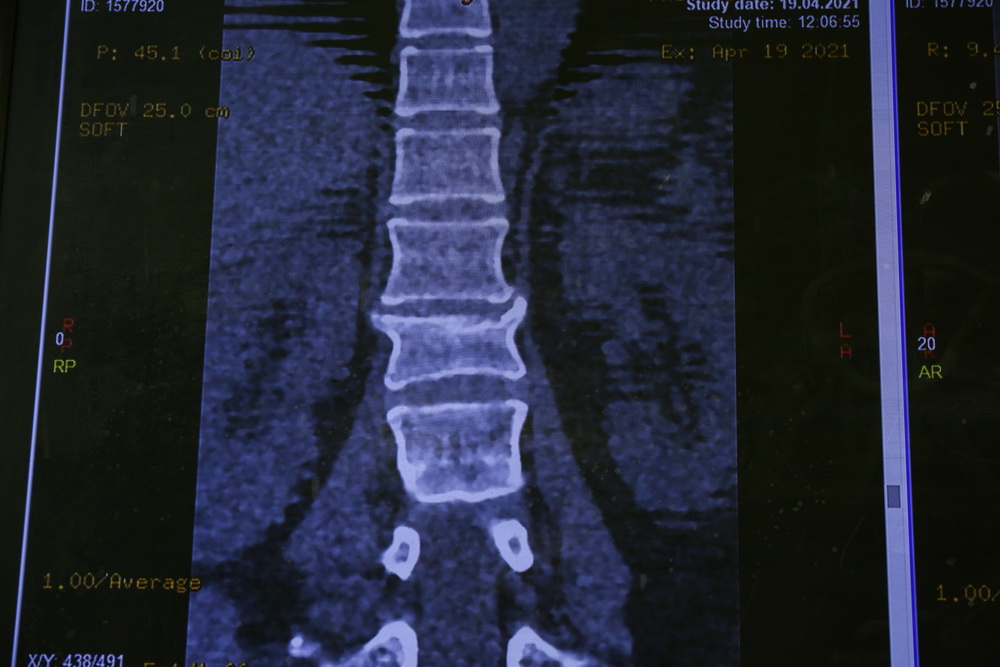

Для начала пациента осматривает бригада специалистов, далее по показаниям проводят дополнительную лучевую диагностику: рентгенографию, МРТ, МСКТ. По снимкам врачи уточняют диагноз и определяют тактику лечения. Не при всех травмах требуется оперативное лечение, только при самых тяжёлых.

Искривление позвоночника ― главный симптом сколиоза. При таком заболевании позвоночник скручивается вокруг вертикальной оси и деформируется во всех трёх плоскостях. В семи из десяти случаев с искривлением сталкиваются девочки.

Часто оно настолько незначительное, что пациентка без проблем живёт с ним всю жизнь. А вот в самых тяжёлых случаях нужна операция. Процедуру назначают, если искривление достигло 40-45 градусов.

Перед операцией делают рентген и МРТ позвоночника. После этого врачи определяют тактику процедуры. Во время операции ставят металлическую конструкцию. Её вставляют в позвоночник, а в шурупы вкладывают стержни. Сначала стержни повторяют деформацию, но их разворачивают, и конструкция встаёт по естественным изгибам тела. Потом позвоночник между отдельными шурупами стягивают или растягивают, чтобы он встал ровно.